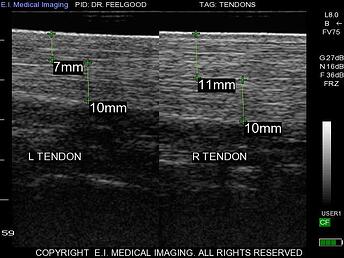

进口牛用B超机IBEX-PRO双重成像—可以通过按键盘左上方的超级键来找到此功能。双图像提供了分屏选项,使您可以并排比较两个图像。这有助于评估双侧结构,例如牛卵巢或狗肾,或有助于将当前图像与以前存储的图像进行比较